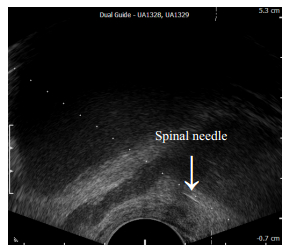

PPNB组在经直肠超声矢状面找到一侧前列腺与精囊腺连接部位,该区域在超声上呈“山峰”征(图 1),经直肠超声穿刺通道置入20 G、长度为7英寸的腰穿针,针尖至“山峰”征部位(图 2),回抽无血后注入1%利多卡因5 mL,B超可观察到前列腺及精囊腺与直肠壁逐渐分离(图 3,4)。相同方法对另一侧前列腺与精囊腺连接部位的前列腺周围神经进行麻醉。麻醉结束后,采用巴德活检枪和18G一次性穿刺活检针行12针系统穿刺活检。非PPNB组不采用任何麻醉,直接行穿刺活检。穿刺标本立即用10%福尔马林溶液固定后送检。

图 2 前列腺周围神经阻滞麻醉示意图 Figure 2 Schematic diagram of PPNB. A 20-gauge, 7-inch spinal needle is placed through the biopsy guide channel under ultrasound guidance into the Mount Everest space where the course of periprostatic nerves pass through. |

图 3 经直肠超声前列腺穿刺麻醉 Figure 3 Sonogram of a 20-gauge, 7-inch spinal needle placed through the biopsy guide channel under ultrasound guidance into the area of the Mount Everest space, where 1% lidocaine was injected. |